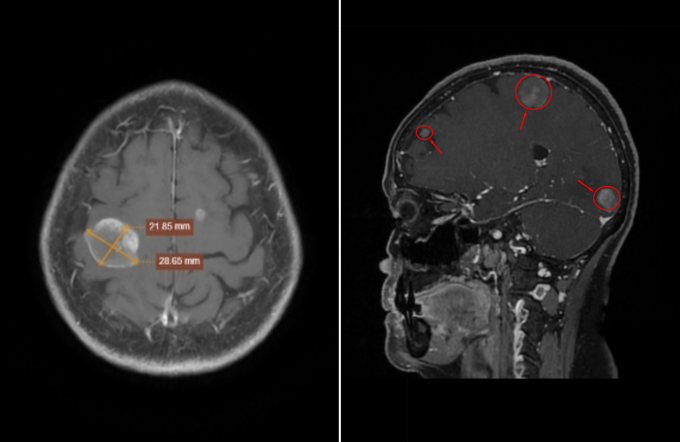

BS.CKII Nguyễn Văn Phúc, Trưởng khoa Chẩn đoán hình ảnh, xem hình ảnh MRI nghi ngờ các khối u thứ phát, tức có thể di căn từ cơ quan khác trong cơ thể. Một số khối có kích thước rõ như khối ở thùy chẩm phải khoảng 18x19 mm và khối ở thùy đỉnh phải khoảng 21x28 mm. Song, cấu trúc não vẫn giữ vị trí bình thường, chưa ghi nhận dấu hiệu chèn ép nên người bệnh chưa xuất hiện triệu chứng thần kinh rõ ràng.

Ảnh chụp MRI não bằng hệ thống 3 Tesla Signa Hero cho thấy các khối u di căn xuất hiện tại não. Ảnh: Phòng khám Đa khoa Tâm Anh Quận 7